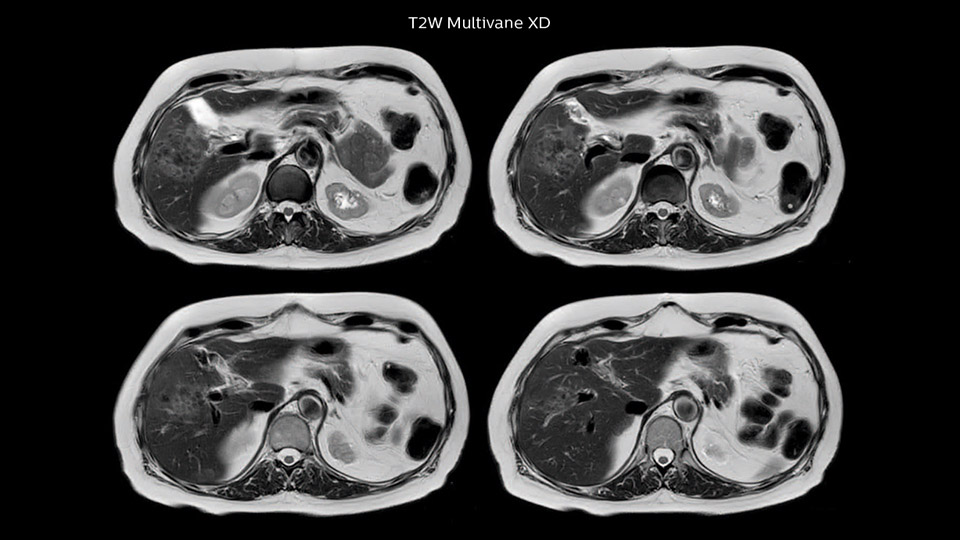

Dr. Baumann then implemented MultiVane XD for motion correction. It uses an extended reconstruction algorithm for imaging that is virtually motion free. “With MultiVane XD we get excellent motion-corrected images with high spatial resolution. We typically first optimize our scan for high image quality, and when satisfied with that, we try to reduce the scan time. So, we combined MultiVane XD with dS SENSE, which allows us to shorten the scan time,” he explains. “The performance of MultiVane XD in liver imaging is outstanding. MultiVane XD with dS SENSE is a powerful development in improving liver image quality.” “As we use breathhold imaging for T2-weighted liver scans, we depend on the patient’s ability to cooperate with the exam. This can present a real challenge when we are looking for small lesions, such as in our oncological patients. However, with MultiVane XD motion correction, we get excellent images. This is important for our surgeons, because they want to know exactly where the lesions are.”

In this example the image quality of the MultiVane XD images is evidently better than in the images without MultiVane XD. Ingenia 1.5T with dS Torso coil solution.

“Our liver exams are quite fast,” says Dr. Baumann. “If the patient tolerates it, we use an arms-up position to reduce the FOV and speed up the exam with dS SENSE.” “We acquire one transversal high resolution T2-weighted sequence with 3 mm slice thickness, for example for pancreas or liver lesions. Then we also add a T2 fat suppressed MultiVane XD SPIR sequence. We perform these two routinely in our liver imaging. We use high dS SENSE factors to significantly shorten scan times to 2-4 minutes, which can improve our protocol; it’s a very robust scan.” “We include mDIXON for the dynamic sequences because of the robust and homogeneous fat suppression we get with that. We had been using eTHRIVE, but we are now quite happy with mDIXON. Sometimes we use a medication to calm the bowels, to further improve the image quality.”